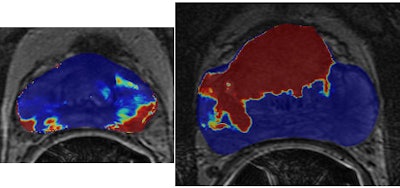

| Sample textural representations found to be highly discriminatory for peripheral zone tumor (left) and central gland tumor (right) show difference in texture with cancer region (green outline) and rest of prostate. |

| Classification heat maps (above) show areas in red that correspond to a high probability of cancer. Green outlines on the previous textural representations correspond well with red regions on the heat maps. The authors found that different classifiers and features performed best for each central gland or peripheral zone cancer. |